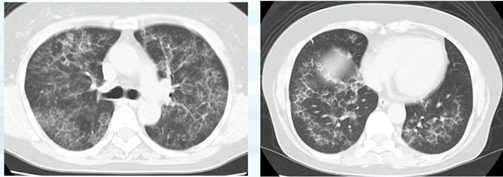

■CT

所見としてはマスクメロン様の網状影、外側が保たれている所見が確認できます。このような場合、肺胞蛋白症を疑います。ここまで確認できれば「肺胞蛋白症疑い」と診断し大病院に精査紹介になります。

※肺胞蛋白症がマスクメロン様の網状影になる理由

蛋白はリンパ路から排出されます。排出すべき液体が増えたためにリンパ路が白く描出されます。リンパ路は肺の外側で発達しているため、排出スピードが速い外側は蛋白が残りません。